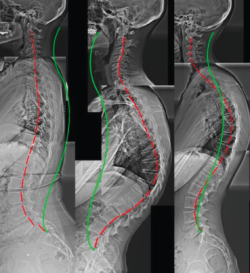

Otros hallazgos radiológicos frecuentes, como las anomalías congénitas de transición lumbosacra, espondilolistesis, secuelas de epifisitis, la espina bífida oculta, las escoliosis leves o moderadas, la hiperlordosis, espondiloartropatía, etc., se encuentran casi por igual en pacientes con y sin dolor lumbar (Figuras 5, 6 y 7)(22,23).

Figura 7. Hiperlordosis. Reproducido de Oakley et al.(23).